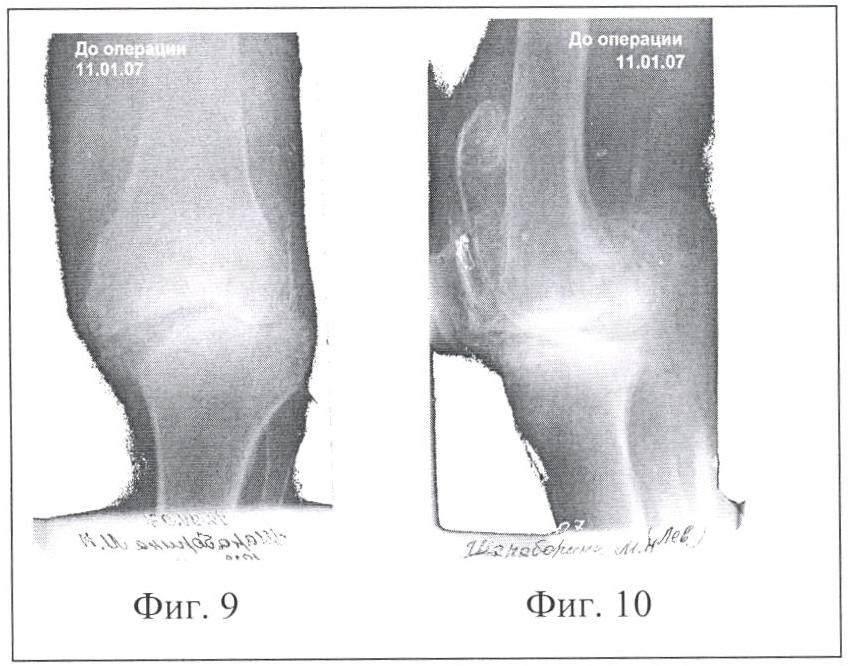

Фиг.9 – Рентгенограмма коленного сустава той же больной до операции, имеется дефект мыщелка большеберцовой кости в прямой проекции.

Фиг.10 – Рентгенограмма коленного сустава той же больной до операции в боковой проекции

Способ оперативного вмешательства осуществляется следующим образом. До операции планируется диаметр фрезы, который должен быть не менее половины ширины суставной щели со стороны оперативного вмешательства, при этом большая часть трансплантата планируется выпиливать со стороны суставной поверхности, имеющей меньший дефект. На фиг.9 и 10 меньший дефект имеет мыщелок бедренной кости. Больной укладывается на операционном столе. Обрабатываются кожные покровы, как перед операцией. На конечность накладывается жгут с целью обескровливания операционного поля. Производится послойный доступ к суставу (ложному суставу). При необходимости производится коррекция вальгусной или варусной деформации сустава с временным фиксированием его спицами. Место для введения цилиндрической фрезы особо не готовится, т.е. не иссекаются связки, рубцы и надкостница. Цилиндрической фрезой выпиливается на заранее запланированную (фиг.1, фиг.2) глубину два разновеликих трансплантата (больший трансплантат берется из менее травмированной кости, имеющей меньший дефект). Оба трансплантата извлекаются или сразу же разворачиваются в образовавшемся туннеле так, чтобы полностью заполнился дефект в кости и перекрыл зону ложного сустава. Импактором по торцу введенных трансплантатов наносятся удары (трансплантаты вбиваются) с целью слегка расширить их («смять», чтобы они плотно сели на место) и сразу же производится остеосинтез каждого трансплантата спицей или винтами, или же винтом обоих трансплантатов с одновременным фиксированием сустава (фиг.5). Вслед за трансплантатами укладываются оставшиеся костные фрагменты или они вбиваются между трансплантатами (если они есть, например, срубленные остеофиты) и рана послойно зашивается до дренажа. Затем производится дополнительная иммобилизация гипсовой повязкой на срок до трех месяцев в зависимости от анатомической области оперативного вмешательства.